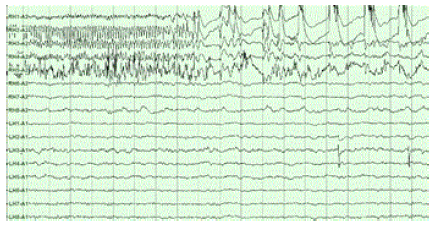

In some cases, déjà vu is more than a funny quirk that passes as quickly as it arrives. For people with temporal lobe epilepsy, déjà vu can be a harbinger of an oncoming seizure. Many people with epilepsy also experience déjà vu before a seizure begins (figure 2) as part of an aura: a perceptual disturbance experienced just prior to a seizure or migraine, such as seeing flickering lights or smelling something that’s not there. Epilepsy patients who experience déjà vu at seizure onset have impaired performance on familiarity and recognition tasks, providing more support that déjà vu is related specifically to familiarity6.

The association of déjà vu with medial temporal lobe seizures also leads to another theory about déjà vu in the healthy brain: the neurological theory. Some scientists believe that since the increased activity in the temporal lobe prior to a seizure causes déjà vu, non-epileptic déjà vu is also caused by a burst of activity in the temporal lobe, like tiny seizure. In fact, scientists have actually been able to induce déjà vu by electrically stimulating the temporal lobe7.